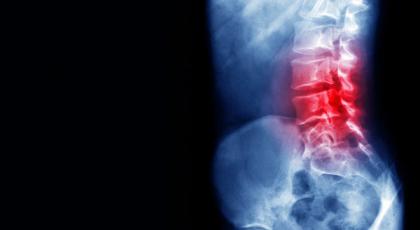

Patient Review 2 - Dr Gaurav Paiwal says "he can heal your low back, neck or knee pain only when you yourself want to finish it off". He is right. He is the best pain specialist in Rajasthan. Best treatment line. No medicines. I am so happy with his treatment. Healed my old back pain totally. Best physiotherapy hospital in udaipur Best physiotherapist in udaipur Best physiotherapy centre in udaipur